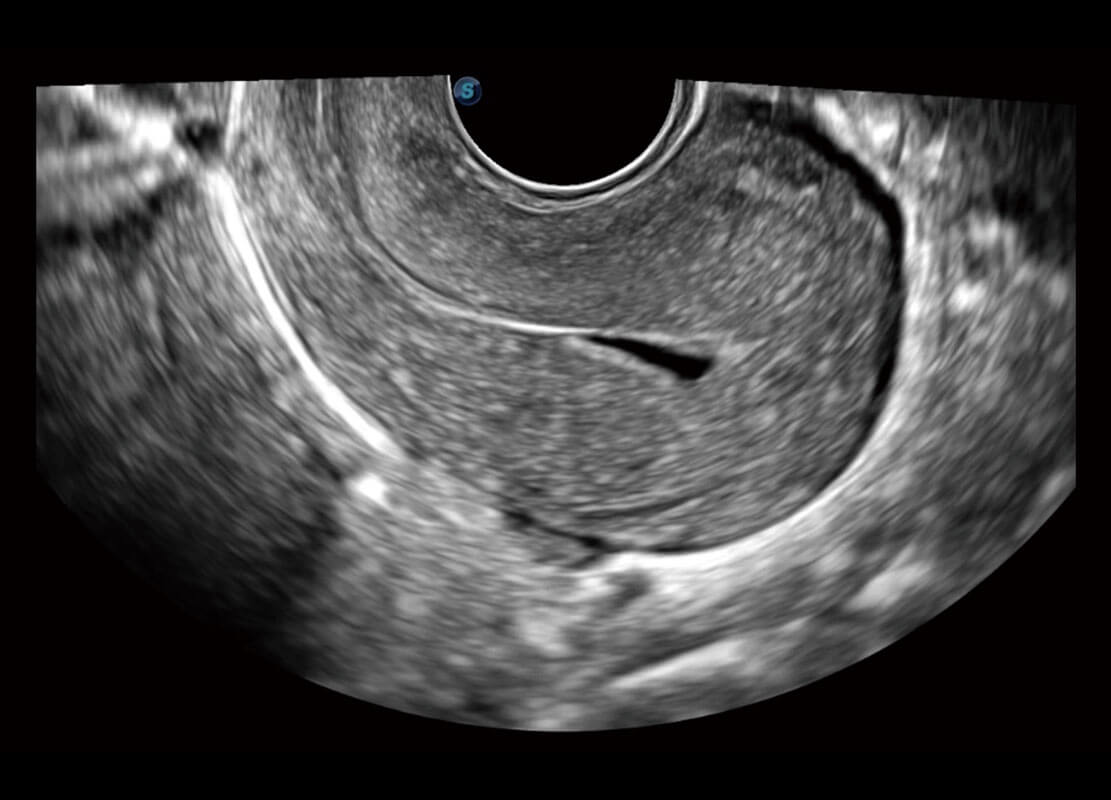

腔内三维-光影成像

P60优异的图像质量搭载专科探头,在妇科基础疾病的诊断、卵泡生长的监测、输卵管通畅情况的判别等方面为您提供生殖应用方案。